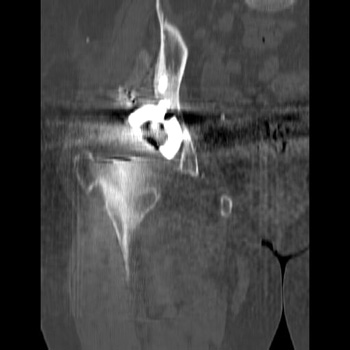

Mass in patient with modular endoprosthesis placed after resection of femur for osteosarcoma. Axial (fig A) and coronal reformatted images (fig B) clearly demonstrate mass adjacent to modular endoprosthesis. 14 gauge core needle biopsy performed under CT guidance (fig C) demonstrated recurrent osteosarcoma

Recurrent osteosarcoma in patient status post resection of femur and placement of modular endoprosthesis. Axial T1 and STIR sequences clearly demonstrate mass adjacent to endoprosthesis.